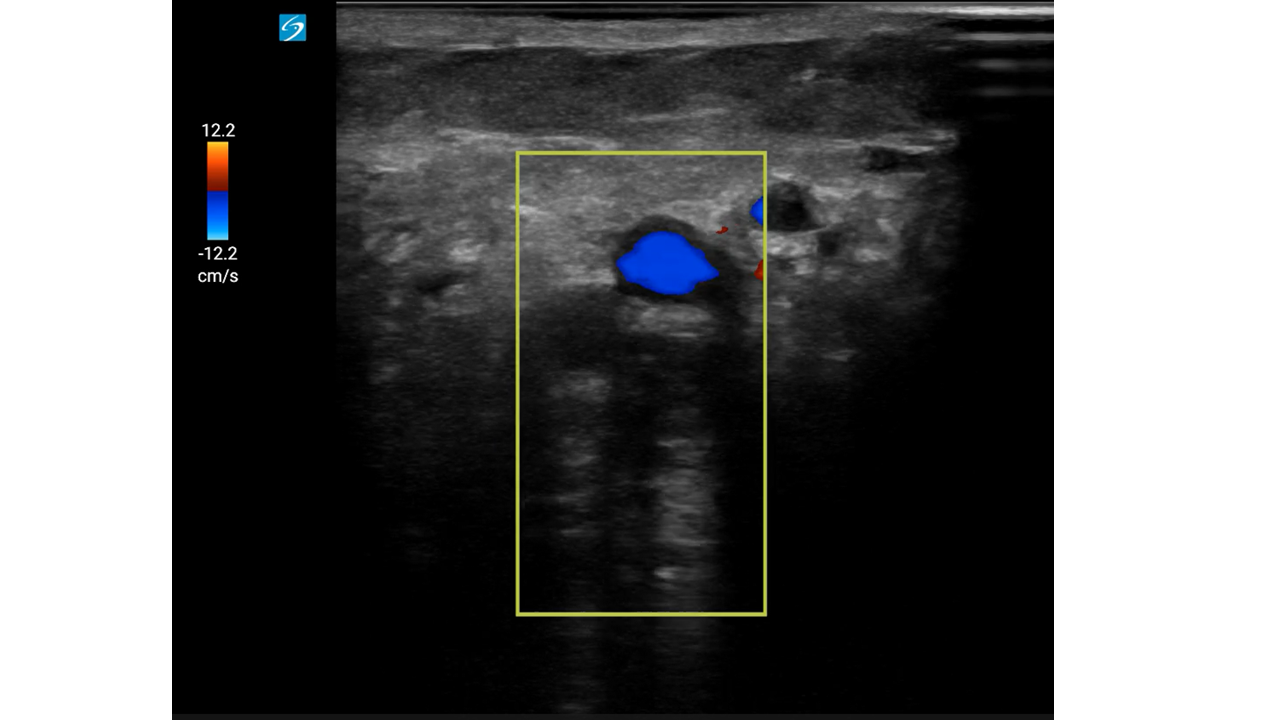

Mujer de 93 años con: fibrilación auricular, enfermedad renal crónica y antecedentes de hemorragias digestivas por las cuales se le había suspendido la anticoagulación oral meses antes.

Motivo de consulta: Dolor súbito, frialdad y pérdida de sensibilidad en la extremidad inferior derecha (EID), con mejoría parcial durante el traslado.

Con mejoría del dolor y pulso poplíteo dudoso, se duda del diagnóstico.

Con sospecha inicial de Isquemia Arterial Aguda (IAA), la mejoría clínica hace dudar abriendo el diagnóstico diferencial a una posible radiculopatía.

Con sospecha clínica de IAA, la ecografía vascular es clave para confirmar el diagnóstico. Su curva de aprendizaje es rápida, se puede utilizar en cualquier punto del sistema y permite derivar al paciente a un centro útil evitando demoras potencialmente fatales.